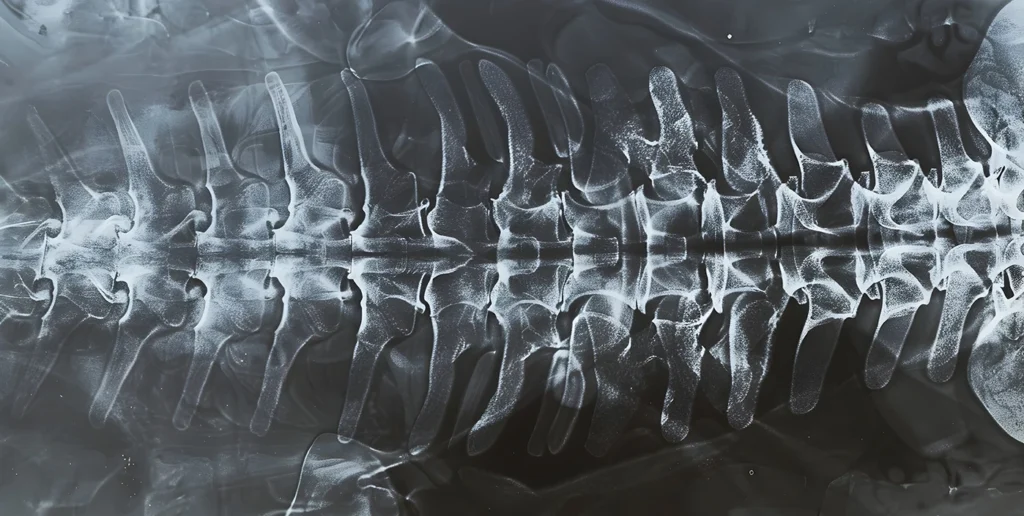

Nuestra columna está compuesta por vértebras apiladas y entre cada una de ellas se encuentran los discos intervertebrales. Estos discos actúan como amortiguadores naturales, permitiendo la flexibilidad y absorbiendo la carga y los impactos. Cada disco tiene una estructura similar a una cebolla: un anillo exterior fibroso y resistente y un centro gelatinoso, conocido como núcleo pulposo.

Una hernia discal ocurre cuando el anillo exterior del disco se debilita o se rompe, permitiendo que el núcleo pulposo se abulte o se escape (se hernie) hacia afuera. Este material herniado puede presionar los nervios cercanos que salen de la columna vertebral, lo que provoca una serie de síntomas dolorosos.

Cuando esto ocurre entre las vértebras L5 a S1, se llama hernia discal lumbar.